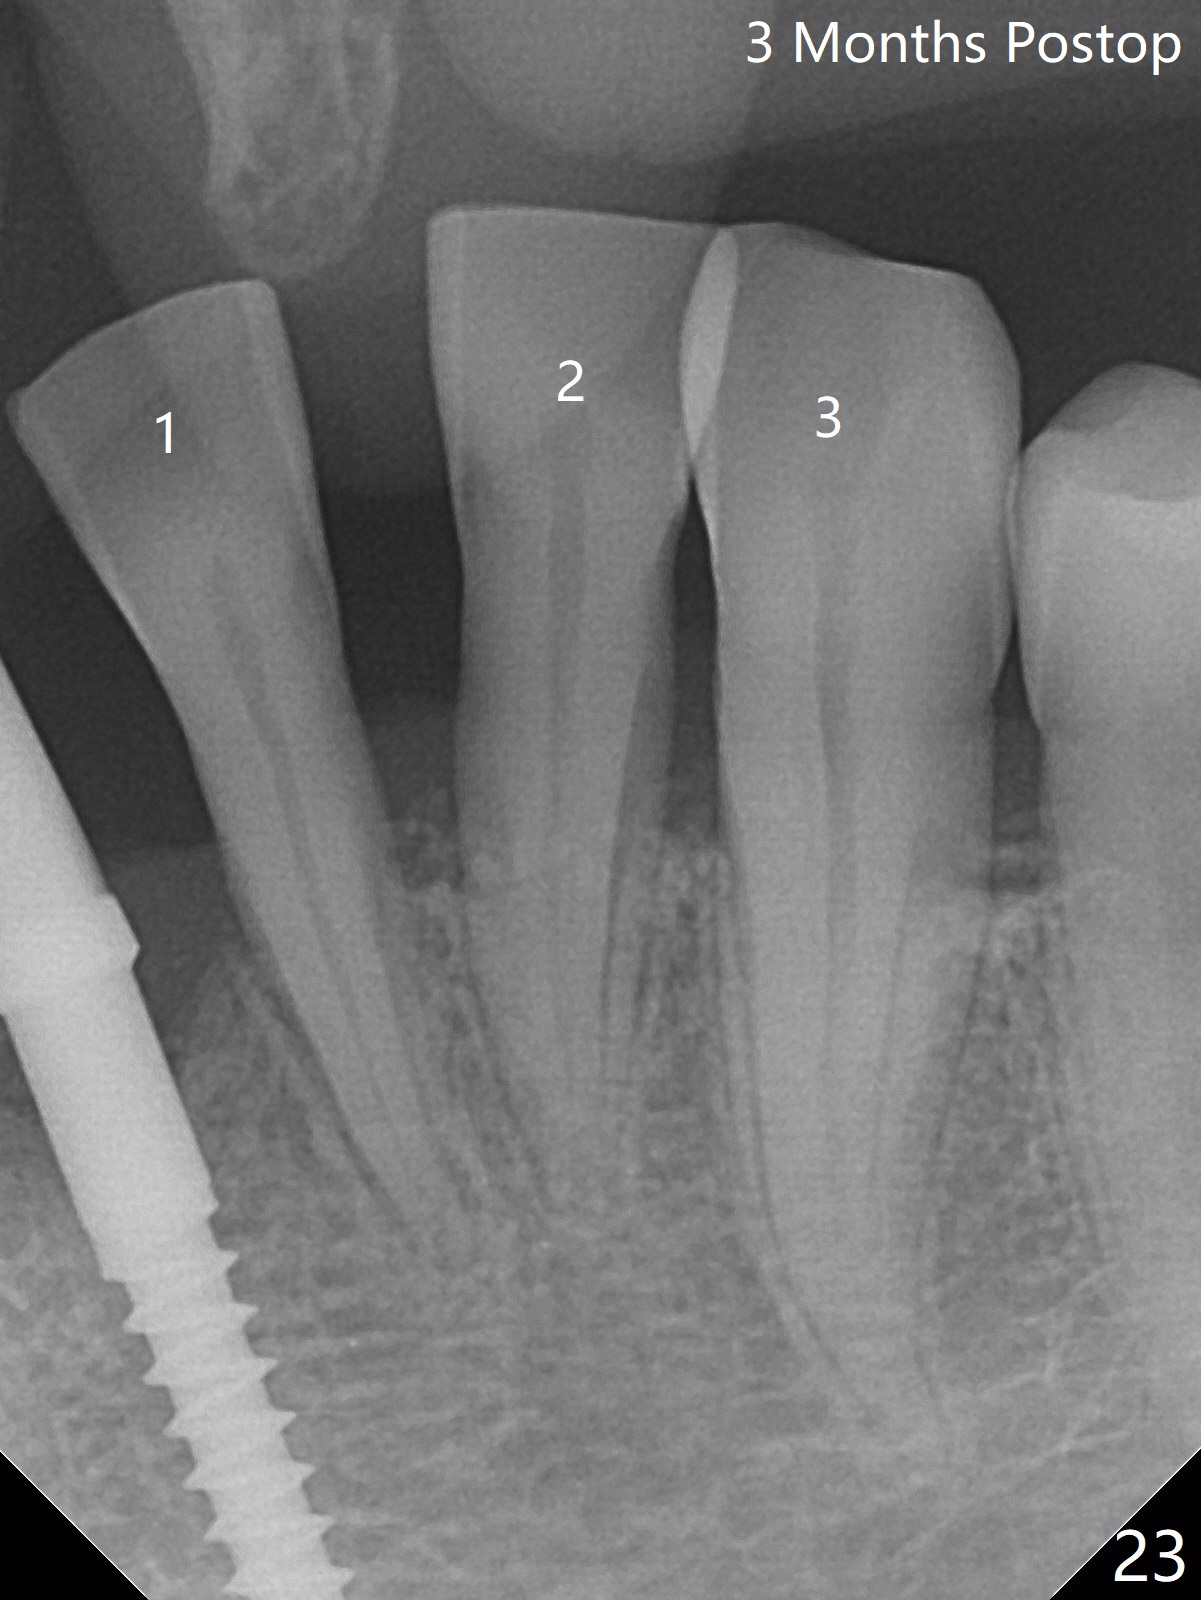

56岁女十分恐惧治疗,缺失右下1,其余切牙由于骨质吸收颊侧移位(图一:1,2),但是她不愿意拔除,同意右下1种植,牙周骨手术,植骨;植体整合后作为支抗,矫正移位下门牙。为了防止忘记舌侧瓣分离,先做舌侧切口(图二),然后颊侧瓣松弛分离(图三),包括使用前牙隧道刀(图四)切断颊侧骨膜,松弛到颊侧瓣能向舌侧牵拉3-4毫米(图五),舌侧瓣骨膜下广泛,深部分离(好像不能切断骨膜,图六),放置导板,磨平狭窄的牙槽嵴(图七:O(osteotomy)),植入2.5x12(4)毫米一段式植体(图八:故意舌侧植入,以便以后矫正),在颊侧骨板打多个出血洞(图八:箭头),然后把在平的器皿上形成的粘性骨板(sticky bone,图九),放置于植体和移位切牙周围(图十),接着使用消毒过的橡皮障punch(图十一(纸头相当于PRF膜;事先给助手示范))在三个PRF膜(图十二)打洞,套在植体和门牙上(图十三: 箭头),防止膜(图十四)和骨块(图十五,十六:*)移位,最后还必须使用最原始方法牙周敷料保护伤口(图十七)。术后9天,舌侧牙周敷料脱落,伤口稍微裂开(图十八)。术后18天撤除敷料,伤口裂开处有新鲜肉芽组织生长(图十九(*:下面是填入的骨粉,将是增宽的牙槽嵴(如果你是乐观主义者)),二十)。病人十分感激我们帮助她度过难关。她的确有sleep apnea,否定tongue thrust。术后三个月植体周围没有明显骨质吸收(图二十一至二十三),左下1,2轻度反合(图二十四),植体周围软组织健康(图二十五),5-5安置矫正器(图二十六,二十七,12 niti)。一周后下切牙向舌侧移动(图二十八),左下1,2反合纠正(图二十九)。再一周变化不大(图三十),植牙圈有些松动,两周后将重做临时牙冠,槽往舌侧移动。结果病人提前回来,植牙槽舌侧移位。一周后右下2不适(图三十一),尝试近中牵引(图三十二)。